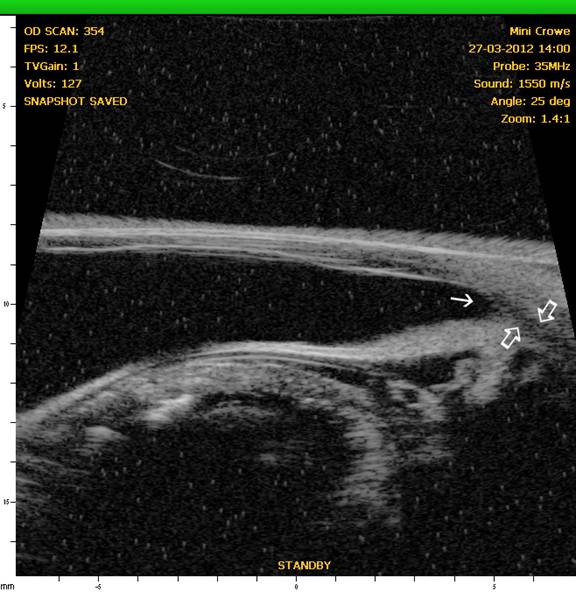

Ciliary Cleft

In recent years, through the use of high-resolution ultrasound (HRUS), we have been able to image the ciliary cleft where aqueous passes after it moves through the iridocorneal angle, and the results have revealed another factor that can contribute to increased intraocular pressure whether the iridocorneal angle is normal or not. In the following figures, note the differences in the ciliary cleft between the right and left eyes of a 10 year-old spayed female Boston terrier. The dog presented for cataracts and had a mature cataract in the right eye and an early immature in the left eye. At the initial examination gonioscopy revealed the iridocorneal angles were normal in both eyes. An electroretinogram was scheduled to evaluate retinal function (since the retina in OD could not be visualized) and prior to dark adaption the pupils were dilated with 1% tropicamide (a short acting anti-cholinergic mydriatic). The intraocular pressures (IOPs) were measured prior to and following dilation of the pupils. Prior to and following dilation the IOP in OD was 18 mmHg whereas the IOP in the left eye was 21 mmHg prior to dilation and 26 mmHg following dilation. HRUS revealed a normal ciliary cleft in the right eye with the mature cataract) and a markedly narrow ciliary cleft in the left eye with the immature cataract (See Figures 5 and 6.). Such occurrences illustrate the potential for problems with dilation of affected eyes as well as for an increased susceptibility for complications following cataract surgery.

Figure 5: OD – HRUS of the anterior segment of the right eye revealing a normal iridocorneal angle (solid angle) and ciliary cleft (open arrows).